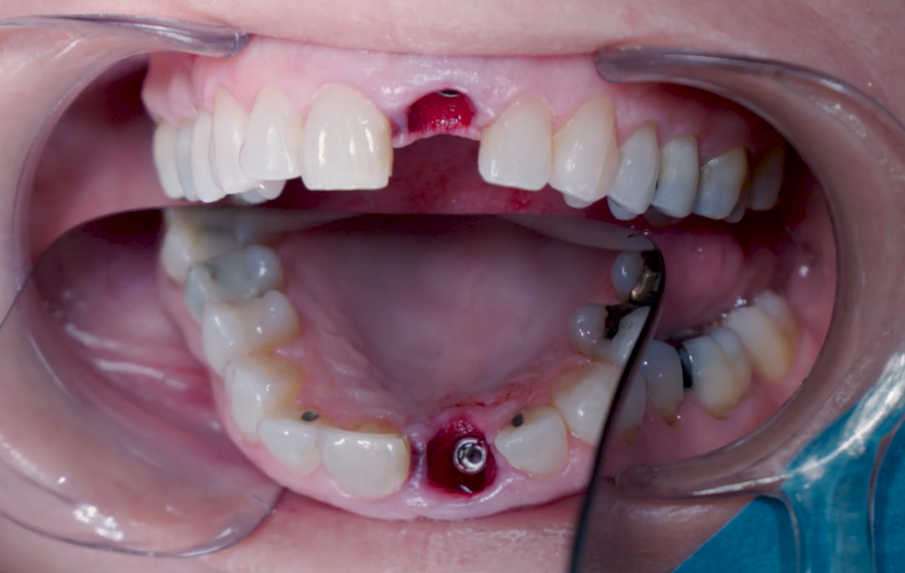

Una paziente di 53 anni si è presentata in studio con un incisivo sinistro fratturato a cui era stata più volte cementata una corona di ceramica (Figg. 1, 2). L’anamnesi e gli esami hanno evidenziato una buona salute sistemica e orale, un’occlusione ben equilibrata e nessuna abitudine al fumo. La tomografia cone beam (CBCT) e la radiografia periapicale hanno mostrato un riassorbimento radicolare esterno con inserimento nell’osso alveolare molto scarso, insufficiente per un adeguato posizionamento di un comune perno endocanalare (Figg. 3, 4). Considerando che il dente fratturato si trovava nella zona estetica, il paziente richiese un restauro nel modo più sicuro e più veloce possibile.

Procedura chirurgica

Sono state eseguite incisioni intrasulculari per liberare le fibre gengivali marginali in modo da consentire un’estrazione minimamente invasiva. L’alveolo è stato accuratamente pulito per rimuovere eventuali residui di legamenti e detriti. Particolare attenzione è stata data alla valutazione dell’integrità della parete alveolare. È stata rispettata una distanza di 3 mm tra il margine gengivale e il margine della parete vestibolare. La preparazione del sito implantare è stata considerata flusso di lavoro osseo di media densità, partendo dalla fresa appuntita in direzione della parete palatale per creare un punto d’ingresso per le frese successive, realizzando un’osteotomia per consentire una più ampia zona di ingresso dell’impianto (Fig. 5).

La fresa preliminare da Ø 2,2 mm è stata utilizzata sulla rispettiva lunghezza prevista dall’impianto, seguita da un perno di allineamento per controllare l’orientamento in 3D (Figg. 6, 7). Le frese da Ø 2,8 mm e Ø 3,2 mm sono state utilizzate per completare l’osteotomia (Fig. 8). Il sito è stato quindi opportunamente sondato per valutare la possibile perforazione della parete. Un impianto 4×14 mm è stato posizionato, a partire dalla maniglia chirurgica che coinvolge la parte apicale dell’impianto, seguendo lo stesso orientamento dell’ago perforatore e correggendo la direzione dell’impianto mentre si spostava all’interno dell’osteotomia (Figg. 9, 10). La stabilità primaria (45 Ncm) è stata raggiunta nella posizione finale.